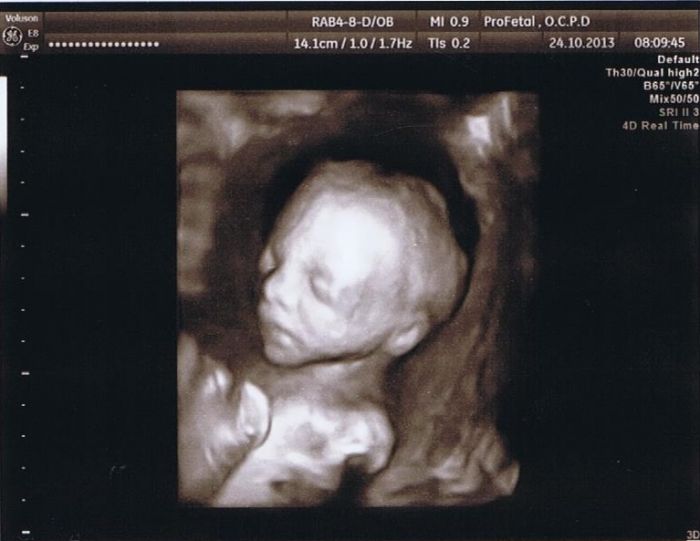

Holky tak máme dnes papírově potvrzenou zdravou holčičku, je to oddych ale to čekání bylo hrozné, byly jsme s přítelem v Hradci Králové, holky tak mě doktor dělal UZ a představte si, že nám přepnul na 4D jen na chvilenku. Jsme se s přítelem lekly, ale byly zvědaví a můžu Vám říct, že první dojem zděšení, jak máme ošklivou holku i přítel se zhrozil, pak už po tom dotočení a zaměření na obličej to bylo pěkný..

My máme ze 4D krásné fotky. Ale když jsem byla předtím v poradně, tak nám to na chvíli taky přepnul na 4D a byla jsem v šoku. Takový ufon s trojúhelníkovou hlavou

Ale za 2 týdny už normální človíček...

V 7 měsíci mají mimča už finální podobu, takže kdo půjde takhle pozdě, bude mít přesnou podobu miminka